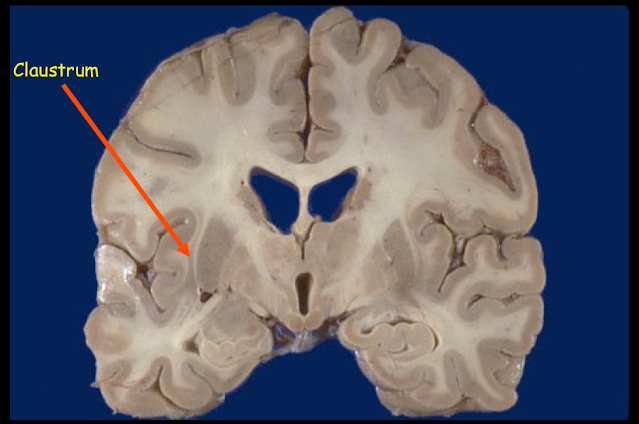

When I was teaching a neuroanatomy class, I used to love slicing a brain in a coronal section with a big brain knife and pointing out the innocuous claustrum to the students around the slab.

The claustrum. This small piece of greymatter is sandwiched between two tracts of white matter (the brain's wiring), the external and extreme capsule. It appears very insignificant but it clearly is not.

I would add, for dramatic effect, "This is where your very soul resides!"which always grabbed their attention and then I would further explain that Francis Crick (of DNA fame) spent his last few years trying to pinpoint the neural correlates of consciousness. He and his team of scientists in the Crick Institute came to the conclusion that the claustrum was the area of the brain that coordinated the activities that led to consciousness. The claustrum connects to every other part of the brain and every other part of the brain connects to it, so this tiny sliver of grey matter is clearly doing something very important (the reticular formation of the tegmentum (floor) of the brainstem is very similarly well-connected but for various reasons it is not thought to be the centre of coordination of consciousness).